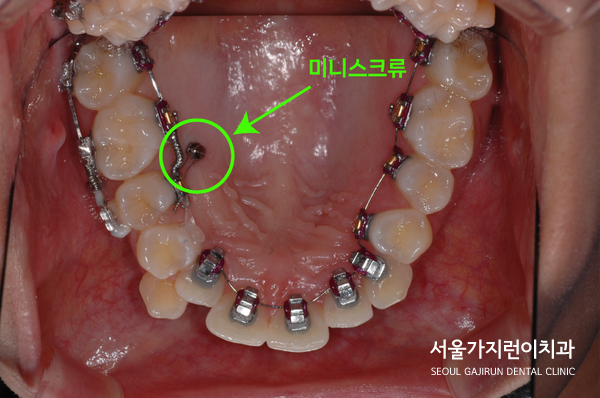

환자 분의 경우 미니스크류를 이용해 상악 우측 어금니를 후방으로 이동시키는 과정을 밟았는데요. 좌측 어금니와의 대칭을 맞추기 위해 진행한 상황입니다. 또 하악의 가지런한 치아배열을 만들기 위해 미니스크류를 적극적으로 활용했는데요. 미니스크류는 치아이동에 필요한 강한 힘을 균등하게 줄 수 있기 때문에 위, 아래 식립한 것을 상기 사진으로 확인해볼 수 있습니다.